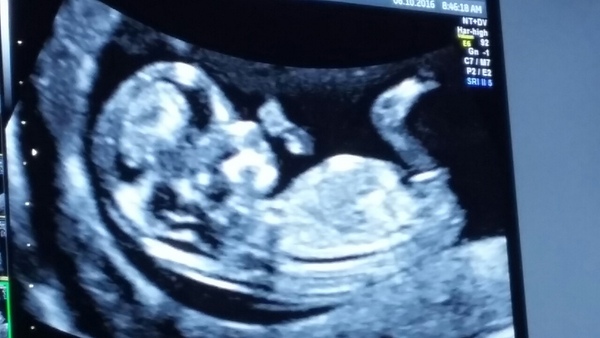

Scan day today. All signs point to normal, which is a huge relief. After having the scan too early last week I can't believe I have to wait until 20 weeks now to see baby again! I'm back slightly to 12+3, due 17 April.

Beep, that's an awesomely clear scan!